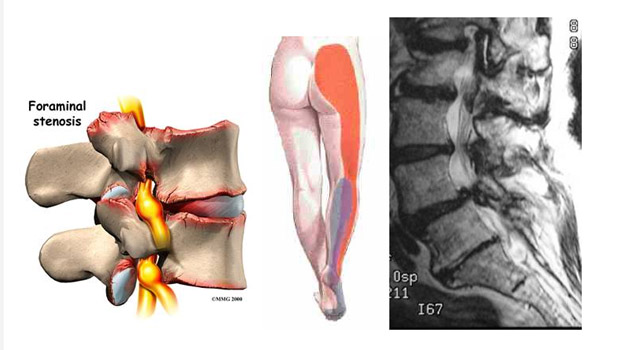

La estenorraquis una afección que compromete la columna lumbar y cervical produciendo síntomas como dolor, limitación de la marcha y alteraciones neurológicas de diferente magnitud, dependiendo del grado de estenosis

(claudicación neurogénica), en la cual el paciente presenta dolor en las extremidades inferiores al caminar algunas cuadras que lo hace detenerse, descansar con la columna flectada para luego continuar la marcha.

Esta puede ser congénita, en la cual el conducto es estrecho desde el nacimiento o adquirida, en cuyo caso se va produciendo con el paso del tiempo por la proliferación de las articulaciones de la columna (facetas y engrosamiento del ligamento amarillo). Cuando se asocia a otros factores como hernias de la columna o discopatias, este estrechamiento produce compresión de la médula espinal y de los nervios raquídeos.

Estos dependen de la estructura nerviosa comprometida. En la columna cervical se presenta dolor en el cuello, hombros y brazos, acompañándose en ocasiones de falta de fuerzas y alteraciones de la sensibilidad. En los casos más severos se produce compresión de la médula espinal, lo que produce alteraciones severas, como alteraciones de la marcha, de la motricidad y sensibilidad; y en casos graves, compromiso de los esfínteres. Cuando la estrechez se produce a nivel lumbar, se produce dolor lumbar bajo o lumbociática y alteraciones de la fuerza y sensibilidad en las piernas.

En casos severos se produce claudicación neurogénica (dolor en las extremidades inferiores al caminar pocas cuadras). Estos síntomas suelen ser lentamente progresivos pudiendo llegar a ser invalidantes si no son tratados a tiempo.

Este se realiza mediante una adecuada historia clínica, un examen físico y neurológico meticuloso y se confirma con exámenes como la resonancia magnética o el escáner. Los exámenes determinan con precisión la región afectada (columna cervical o lumbar) y la severidad de ésta.